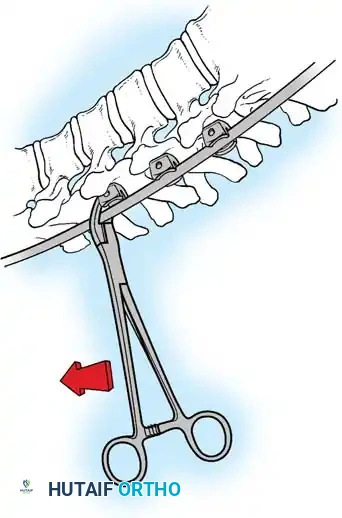

Lateral Exposure and Hemostasis

- Transverse Process Exposure: Extend the subperiosteal dissection laterally, first exposing the facet joints, and then continuing out to the tips of the transverse processes bilaterally.

- Segmental Vessels: As you dissect lateral to the facet joints, you will encounter the posterior branches of the segmental vessels. These must be meticulously identified and coagulated with bipolar or monopolar cautery to prevent insidious bleeding.

Fig. 38-24: Posterior view of segmental vessels located just lateral to each facet joint, requiring meticulous coagulation.

- Facet Cleaning: Use a sharp curet and a pituitary rongeur to completely excise the facet capsules and clean the interspinous ligaments.

Clinical Pearl: Always direct your curet from the midline laterally when cleaning the facet joints. This directional force ensures that if the instrument slips, it moves safely away from the spinal canal, preventing catastrophic dural tears or iatrogenic spinal cord injury.